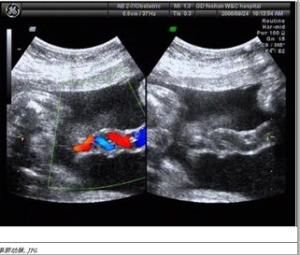

正常的是彩色都卜勒示一紅兩藍或兩紅一藍的彩色血流信號呈“麻花狀”排列。

而單臍動脈的是彩色都卜勒血流顯示一紅一藍盤曲伴行分布。

正常臍帶是含兩根動脈和一根靜脈,那么切面就是品,單臍呢就是單動脈和一根靜脈,切面就是呂字